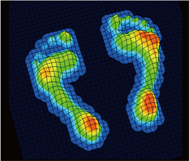

歩行検査

片方ずつの足でプレートを踏んで歩行し検査します。

圧力中心線の軌跡や歩行周期を動画で記録できます。

計測画面

足長、足幅、角度の計測が行えます。圧力中心線の軌跡から回内足、回外足等の歩行異常の分析が行えます。

フレーム分布

歩行時の接地状態を0.06秒毎のコマ送りにしたデータです。左右のフレーム数の違いから被験者へ荷重時間の差を視覚的に説明する事が出来ます。